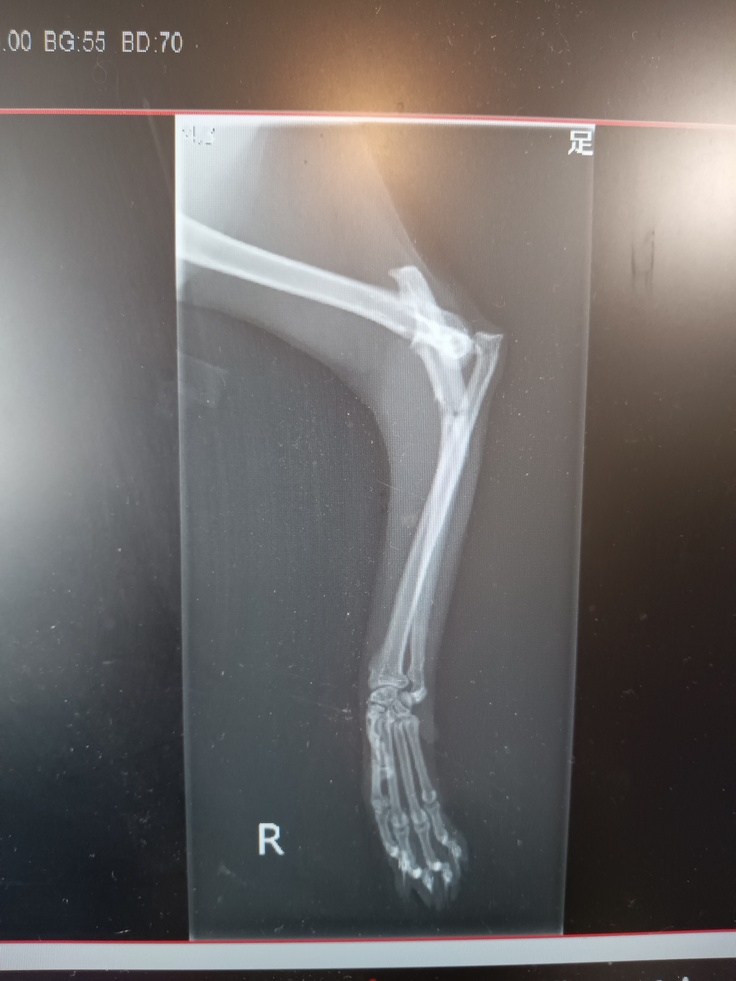

夜9時頃夜間動物病院に連れていき、レントゲンを撮ってもらったところ右足の骨が骨折し、脱臼してるいることが分かりました。

↑レントゲン写真です